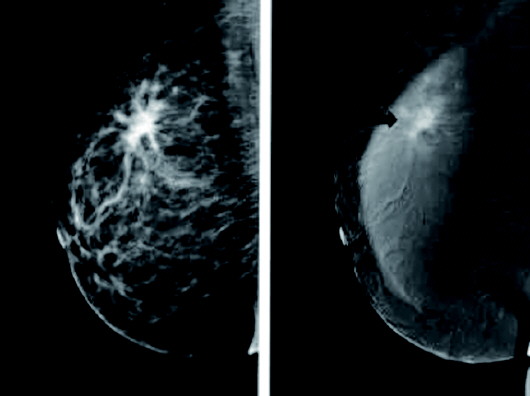

近日,济阳区中医医院引进一台最先进、最高端的美国GE公司生产的乳腺疾病诊断专用检测设备,具有常规摄影、增强(CESM)及定位穿刺活检治疗三合一的高级功能,是国内最先进的乳房检测设备,也是诊断早期乳腺癌的金标准;它可作为一种无创性的检查方法,比较全面准确地反映出整个乳房的结构。能够比较可靠地鉴别出乳腺的良性病变和恶性肿瘤。该项检查操作简便,分辨率极高,不受年龄、体形的限制,无创伤,它可以检测出医生触摸不到的乳腺肿块,特别是针对大乳房和脂肪型乳房,其诊断性极高。

这是因为该设备可检出直径小于1mm的早期癌,甚至可以发现微小的原位癌,能够可靠的进行乳腺癌的早期筛查。定期做该项检查能够比经验丰富的医生触诊早两年发现乳癌,能够使乳癌的死亡率降低20%-40%。对于少许微小钙化为唯一表现的早期乳腺癌(临床检查为阴性),也能凭该项检测被早期发现和诊断,尤其对于临床不可能及的,以微小钙化簇为唯一表现的早期乳腺癌具有特征性的诊断意义。该仪器检查诊断可准确钙化的形状、大小、密度、性质等。对于彩超无法辨别的乳腺病变钙化点进行准确判断与鉴别,被誉为国际乳腺疾病检查的金标准。